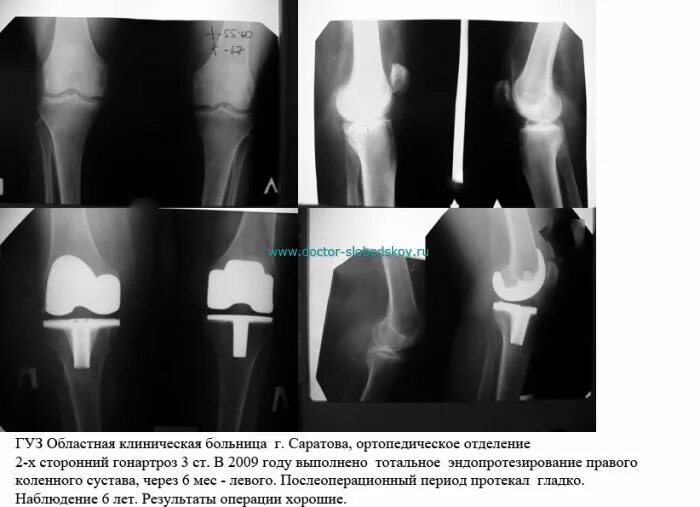

После эндопротезирования 2 суставов прошло